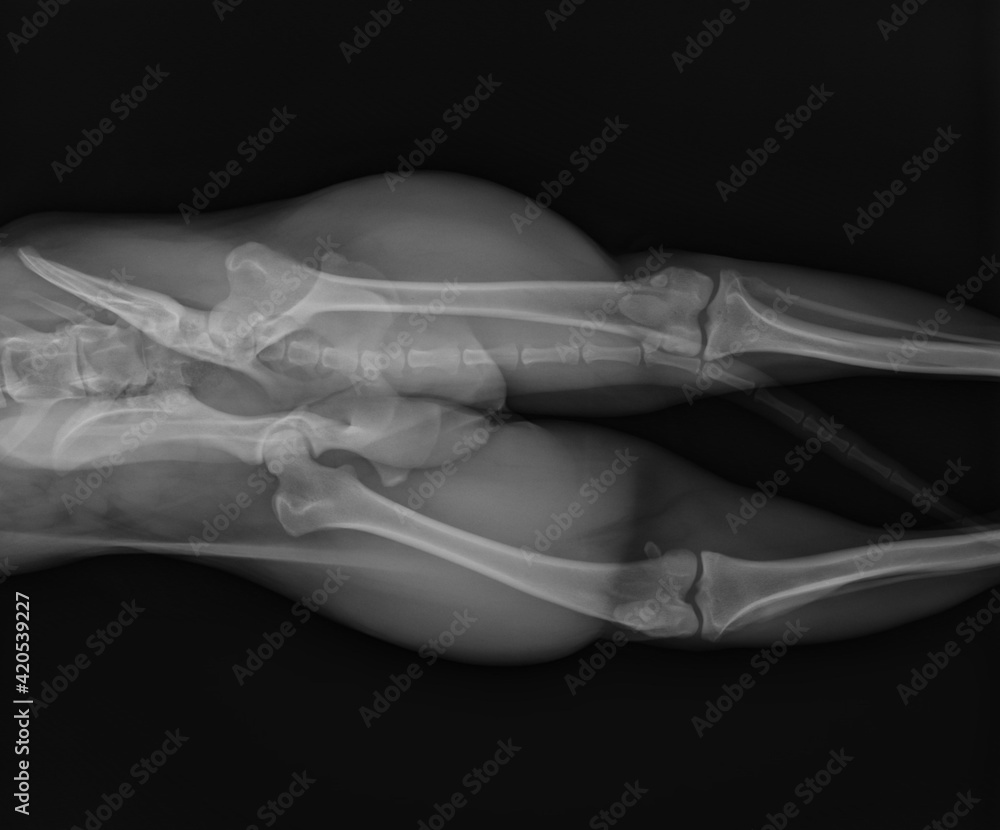

Dog X Ray Showing Hip Luxation Right Leg Lateral View Stock Photo Sock In Dog X Ray If left untreated, foreign body ingestion can lead to. this article provides examples of radiographically detectable foreign bodies in dogs and cats. left lateral radiograph of a young dog with mechanical obstruction caused by foreign material. (1) take him to either your vet or animal emergency hospital if… Learn what other objects are dangerous or safe for. . Sock In Dog X Ray.

Dog X Ray Showing Pelvic Fracture Stock Photo Adobe Stock Sock In Dog X Ray socks, underwear, pantyhose, and the like can cause gi obstructions in dogs. Learn what other objects are dangerous or safe for. this article provides examples of radiographically detectable foreign bodies in dogs and cats. left lateral radiograph of a young dog with mechanical obstruction caused by foreign material. (1) take him to either your vet or animal. Sock In Dog X Ray.